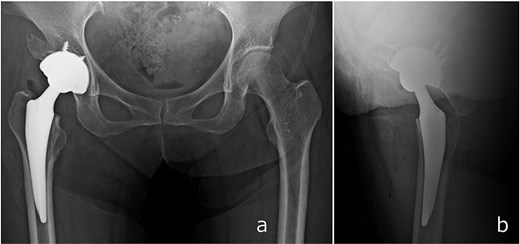

Surgery was performed via a posterior approach. The femoral head fragment avulsed at the ligamentum teres was found incarcerated within the acetabulum. Although fractures of the AIIS and anterior wall were identified, sufficient acetabular coverage and stable press-fit fixation of a cementless cup were achieved without additional internal fixation. A dual mobility cup (DMC) and a cementless femoral stem were implanted (Fig. 4).

Immediate postoperative anteroposterior (a) and lateral (b) radiographs demonstrating stable placement of the total hip arthroplasty components.

Full weight-bearing was allowed from postoperative day 1. The patient regained independent ambulation and was discharged home on postoperative day 28. At 6 months, she had resumed recreational activities with a Harris Hip Score of 92. No complications were observed, and follow-up CT demonstrated healing of the anterior wall fracture and partial union of the AIIS fragment (Fig. 5).